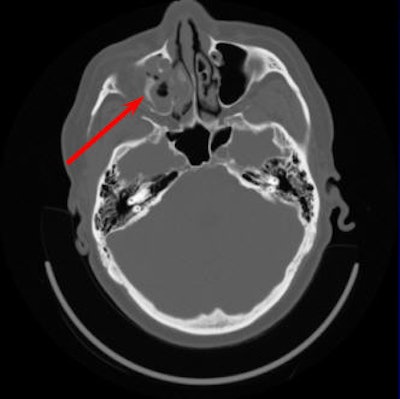

| A right orbital floor fracture that was missed. Ancillary findings should increase suspicion for specific pathology. Blood in a maxillary sinus is a finding on axial images that is highly suspicious for an orbital floor fracture. The fracture itself may be difficult to discern because it is in the plane of imaging. Images courtesy of Dr. Barton Branstetter IV. |